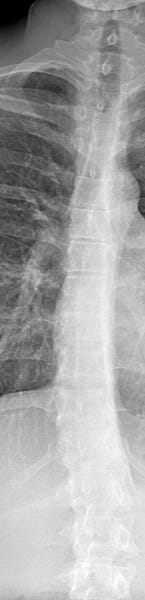

Cual es el tipo de mi escoliosis en es o en c

Es en es o c mi escoliosis por favor alguien sabe de cual tipo es

La escoliosis es una curvatura anormal de la columna vertebral que puede ocurrir en diferentes formas y grados de severidad. No existe una clasificación universalmente aceptada para categorizar los diferentes tipos de escoliosis, pero en general, se pueden distinguir varios tipos según la causa subyacente, la ubicación y la forma de la curvatura.

En cuanto a las diferencias entre la escoliosis tipo C y tipo O, cabe destacar lo siguiente:

• Escoliosis tipo C: se refiere a una curvatura lateral de la columna vertebral que se produce como resultado de una anormalidad en las vértebras cervicales (cuello). En la escoliosis tipo C, la curvatura suele ser leve y no suele progresar con el tiempo. En algunos casos, la escoliosis tipo C puede ser una manifestación de un trastorno del desarrollo óseo, como el síndrome de Klippel-Feil.

• Escoliosis tipo O: se refiere a una curvatura lateral de la columna vertebral que se produce como resultado de una anormalidad en las vértebras torácicas (parte superior de la espalda). La escoliosis tipo O es más común que la tipo C y puede ser causada por una variedad de factores, incluyendo trastornos genéticos, neuromusculares o metabólicos. La curvatura en la escoliosis tipo O suele ser más pronunciada que en la tipo C y puede progresar con el tiempo si no se trata.